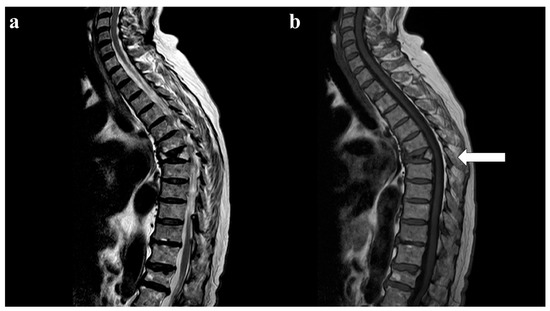

- von Kalle, T.; Heim, N.; Hospach, T.; Langendörfer, M.; Winkler, P.; Stuber, T. Typical Patterns of Bone Involvement in Whole-Body MRI of Patients with Chronic Recurrent Multifocal Osteomyelitis (CRMO). Rofo 2013, 185, 655–661. [Google Scholar] [CrossRef]